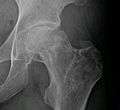

X-ray images of avascular necrosis in the early stages usually appear normal. In later stages it appears relatively more radio-opaque due to the nearby living bone becoming resorbed secondary to reactive hyperaemia.[1] The necrotic bone itself does not show increased radiographic opacity, as dead bone cannot undergo bone resorption which is carried out by living osteoclasts.[1] Late radiographic signs also include a radiolucency area following the collapse of subchondral bone (crescent sign) and ringed regions of radiodensity resulting from saponification and calcification of marrow fat following medullary infarcts.

Radiography of avascular necrosis of left femoral head. Man of 45 years old with AIDS.